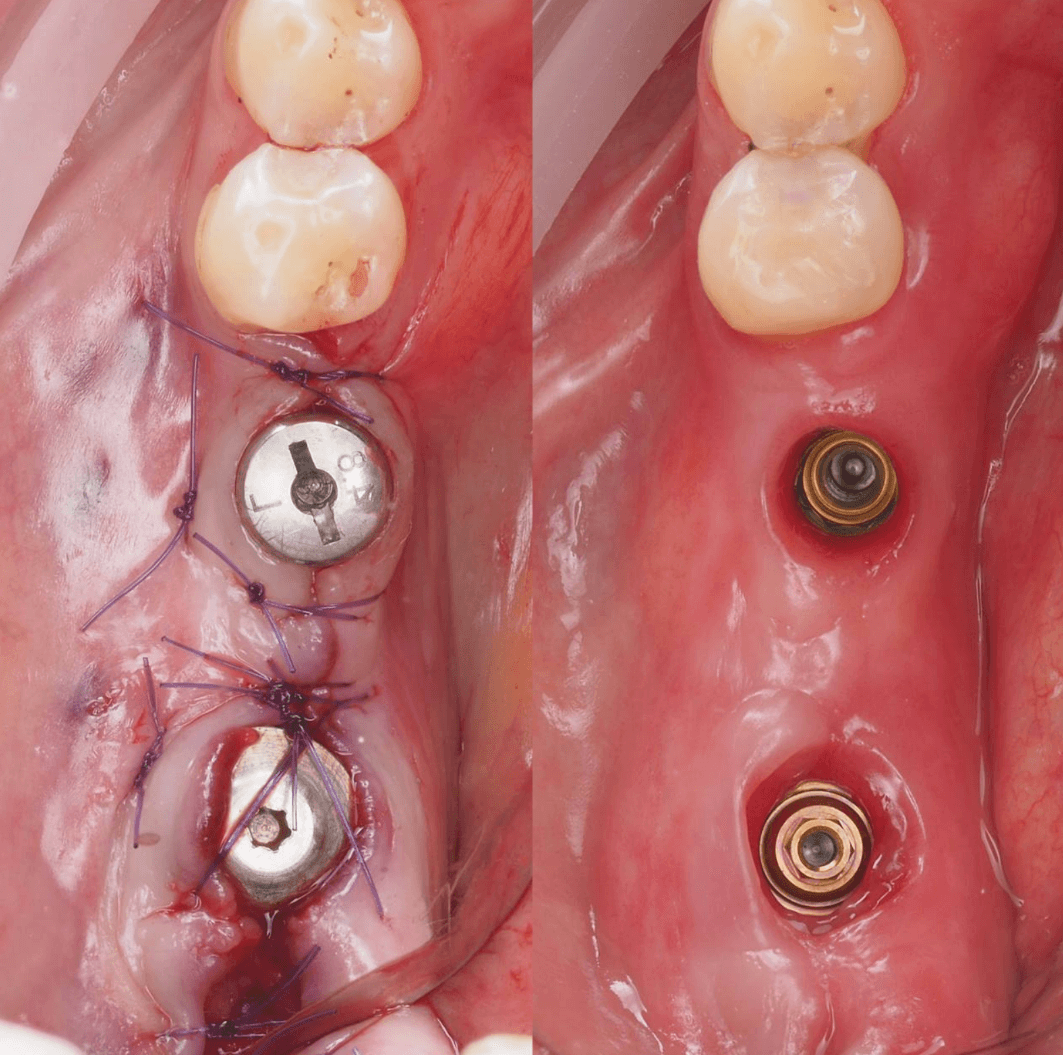

В область отсутствующей шестерки был установлен AnyOne Onestage Tussue Level, а в лунку моляра – широкий AnyRidge + мультиюнит с высотой десны 2,5 мм. Далее пластика мягких тканей.